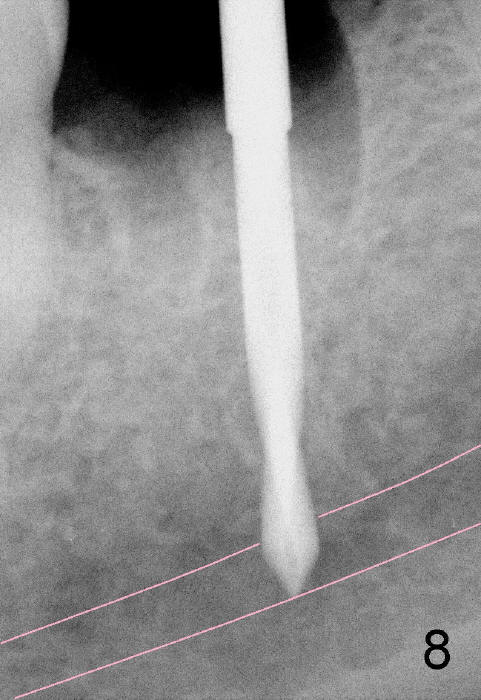

Septal bone is apparently pushed into the mesial and distal sockets (Fig.7 inset arrows) when a small round osteotomes is removed. The deeper portion of osteotomy is created by drills (Fig.8,9). The septal bone is further pushed mesiodistally as the osteotomy enlarges with combination of drills and osteotomes (Fig.10). A 6x17 mm tapered implant is placed with insertion torque >60 Ncm (Fig.11: I).